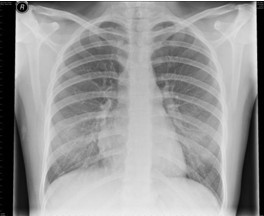

4.胸部X線檢查 哮喘發(fā)作時(shí)兩肺透亮度增加,呈過(guò)度充氣征象:并發(fā)肺部感染、肺不張、氣胸時(shí)出現(xiàn)相應(yīng)X線征象。

【題】下列哪項(xiàng)描述符合哮喘發(fā)作時(shí)典型的X線表現(xiàn)

A.兩肺透亮度增加,呈過(guò)度充氣征象

答案:本題選A。